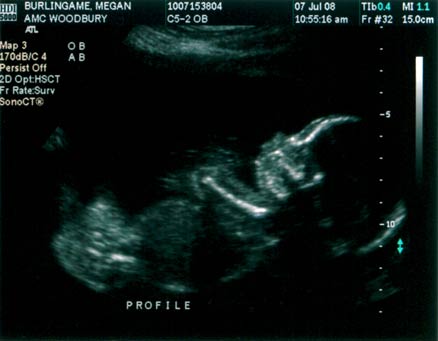

BOY!!! The B’s now have a boy to go with my brother’s girl. The ultrasound went well; the baby looked good. According to the ultrasound measurements, the computer calculated a new due date of November 12. I’m not sure if one date is more accurate than other (11/20 was the initial due date), or if it’s more of a ballpark type of thing. Either way, it’s going to be very close to hunting season (Nov. 8-16). Below are a couple of the ultrasound pics. Click the images for high-res versions.